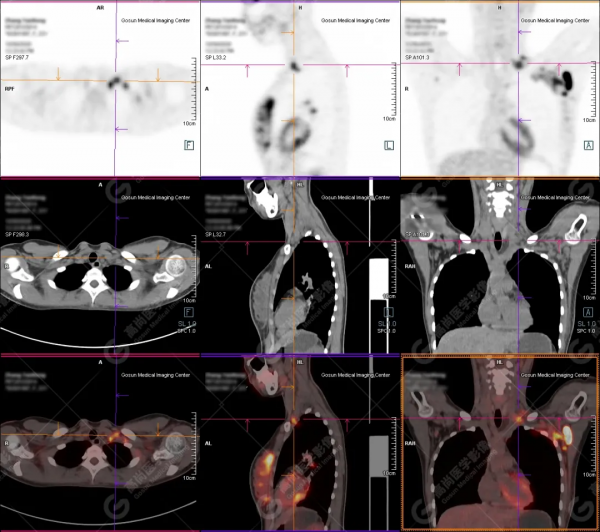

病例二

病史:患者26歲,年輕女性。

腰痛1月入院,發現乳腺結節。

腫瘤標誌物均正常。

B超提示左乳佔位。

既往經期正常,餘無特殊。

檢查所見:

PET/CT提示:

左側乳腺外上象限團塊狀高代謝病灶,考慮為乳腺癌。

左側腋窩、雙側肺門及縱隔(5組)多發淋巴結轉移。

雙肺內多發轉移。

顱蓋骨、顱底骨、雙側鎖骨、雙側肩胛骨、胸骨、雙側多處肋骨、脊柱椎體及附件、骨盆諸骨及雙側股骨上段廣泛多發骨轉移。

病理穿刺:

左側乳腺導管癌。